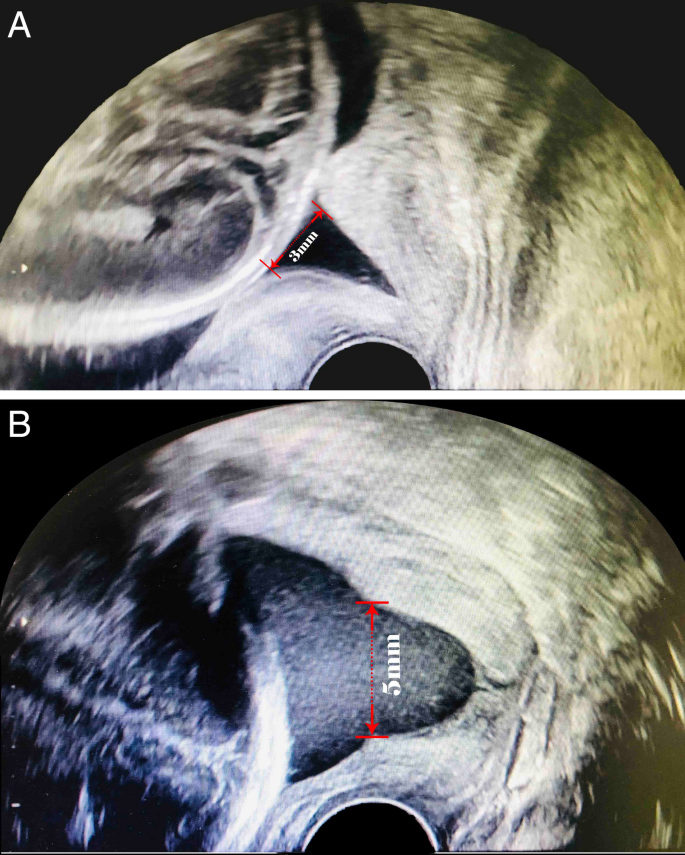

The ultrasound measurements were in accordance with a unified standard. All patients underwent transvaginal cervical length (TVCL) measurements between 20 and 24 weeks when the optimal image of the cervix was relatively easy to capture. The TVCL measurements of all subjects were performed by experienced sonographers at our ultrasound units. The ultrasound assessment was performed to measure the length of the cervical canal from the internal OS to the external OS and observe whether cervical funnelling appears with patients in the lithotomy position with an empty bladder. The measurement was repeated under gentle fundal pressure or the Valsalva maneuver unless severe cervical shortening was observed. Each examination was performed for at least 3 min as an evaluation period to detect the development of a “funnel”, which was defined as the protrusion of the amniotic membrane of 3 mm or more into the internal os as measured along the lateral border of the funnel (Fig. 9)49,50.